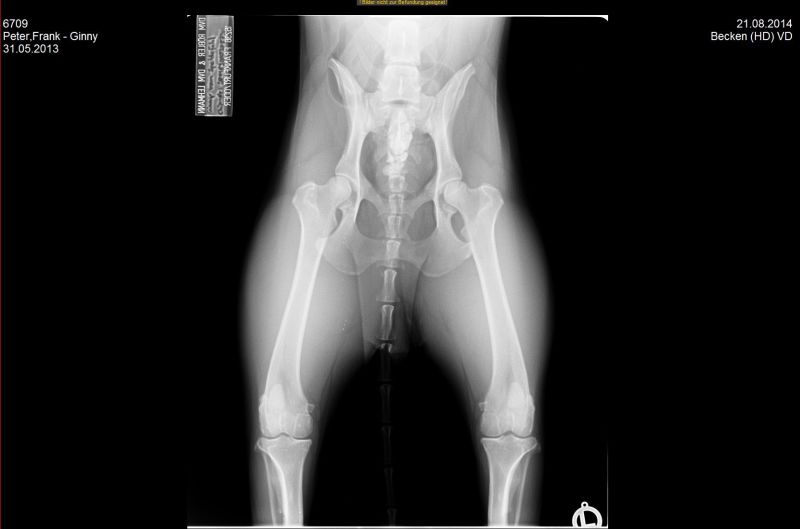

21.08.2014 - Ginny HD-und ED geröntgt - 15 Monate alt

24.08.2014 - Ginny - 15 Monate alt